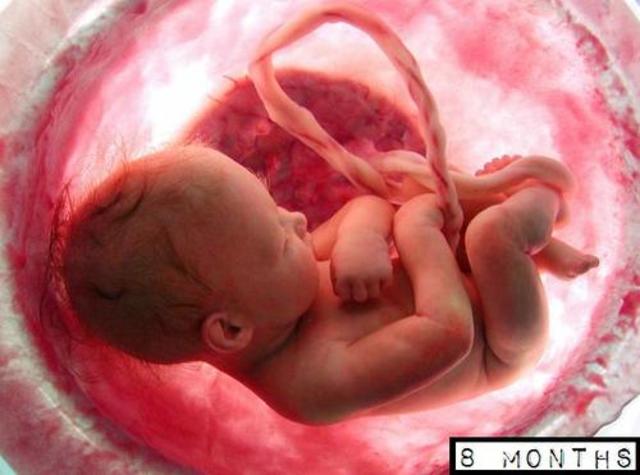

• mature

mature

The brain starts to mature much faster with the activity that greatly resembles a sleeping newborn. The fetus continues to develop, put on weight, and prepare for life outside of the womb. The lungs begin to expand and contract, preparing the muscles for breathing. this domain is physical

• newborn baby

newborn baby

all the stages of prenatal development are done and now it is time to welcome a baby to this world. even though this pregnancy went good were lucky no problems went on in these stages. this domain is physical and social